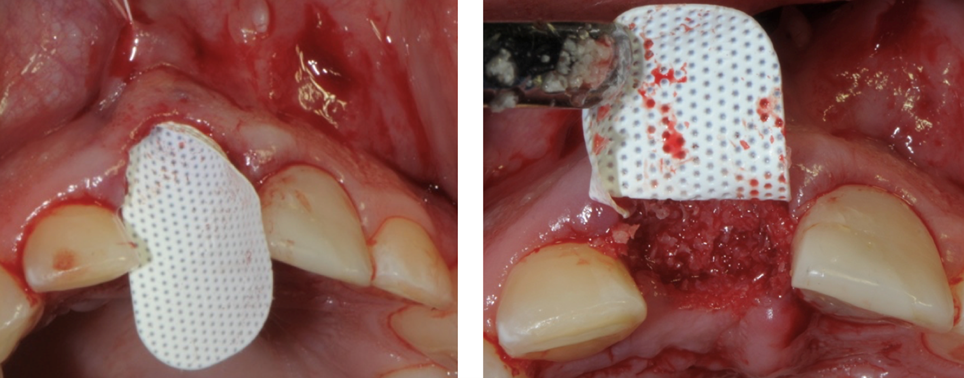

La membrana Cytoplast in d-PTFE viene ritagliata per estendersi di 3-4 mm oltre i margini della cavità e quindi con un curette infilata sotto il periostio del lembo palatale, vestibolare e la papilla interdentale.

Inserimento della membrana in dPTFE Cytoplast TXT 1224 tramite sutura e posizionamento di sostituto osso suino ad alta porosità Zcore™.